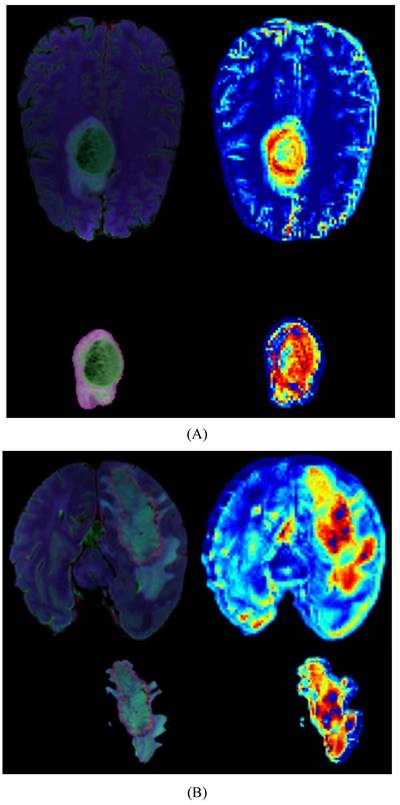

We provide model explainability through heatmaps, as shown in Figure 5. The darker red regions indicate the areas the model focuses on the most. In the original images, the model primarily focuses on the glioma in the brain. Based on the image segmentation results, we retain only the tumor regions as input for the model. The segmented images include necrotic regions, edema areas, and enhanced tumor regions. The heatmaps generated from these segmented images provide a more detailed focus area, and we can observe that the deeper red regions on the tumor correspond to the most prominent areas learned by the model during tumor grading.

Figure 5

Heatmaps for LGG(A) and HGG(B), each map includes a whole-brain map and a tumor map with four modal overlays. The darker red regions indicate the areas where the model focuses most.